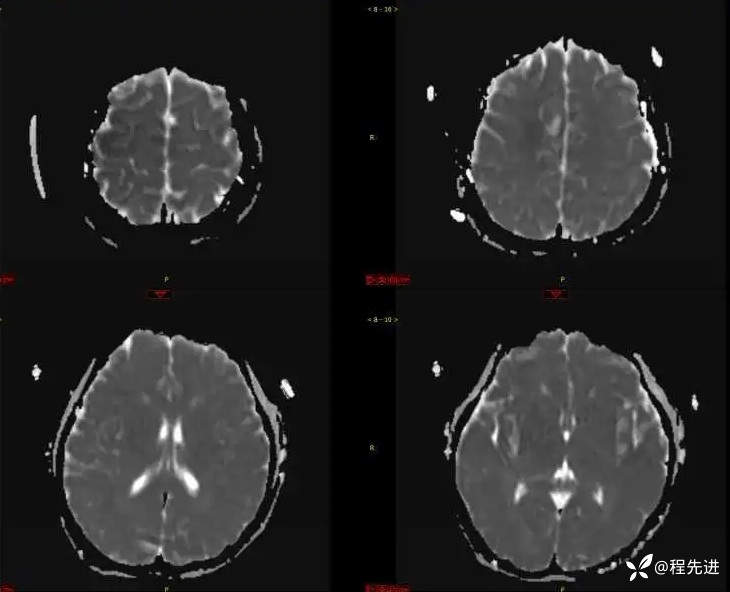

DWI、ADC: